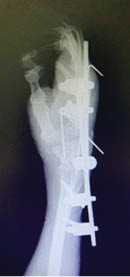

Masculino de 37 años de edad que el día 11/02/2019 recibió agresión por terceras personas con objeto corto contundente, lo que condiciona amputación de mano izquierda, a nivel del carpo (Figuras 1 a 3). La mano es puesta en condiciones apropiadas en un medio húmedo y térmico y el paciente es estabilizado hemodinámicamente en el Servicio de Urgencias. Se realiza el procedimiento con dos equipos quirúrgicos, uno trabajando con la mano y el otro con la extremidad afectada: se realiza un aseo de la extremidad superior izquierda, se inicia con estabilización ósea, posteriormente con la reparación término terminal de la arteria radial y cubital en compañía de sus dos venas respectivamente, se realiza neurorrafia de nervio radial y cubital, se continúa con tenorrafia de tendones flexores y extensores, se retira la isquemia y se corrobora que no haya hemorragia activa; posterior a cuatro horas de evolución se realiza reimplante de mano en cinco horas de procedimiento quirúrgico. No se requirió manejo en Unidad de Cuidados Intensivos, ya que el paciente se encontraba estable (Figuras 4 y 5). Posterior a seis meses, después de seguimiento y tratamiento de rehabilitación, se recupera aproximadamente 70% de la función de la mano, logrando pinzas gruesa y fina funcionales, las cuales le permiten tomar objetos pequeños como un bolígrafo.

Figura 1

Figura 2

Figura 3

Figura 4

Figura 5